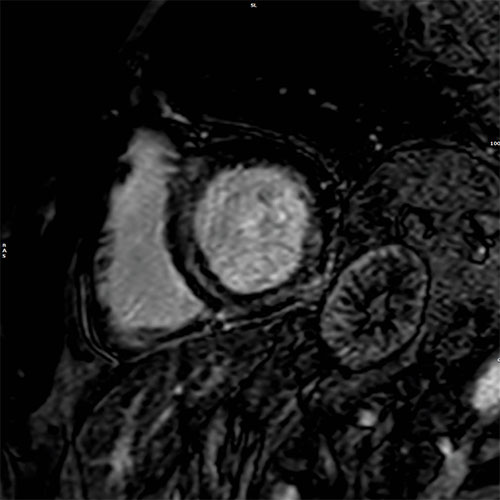

Cardiac MR images of a patient with non-ischemic cardiomyopathy showing delayed enhancement and severe mitral regurgitation.

PSIR – short axis view

EPI cine - 4 chamber view